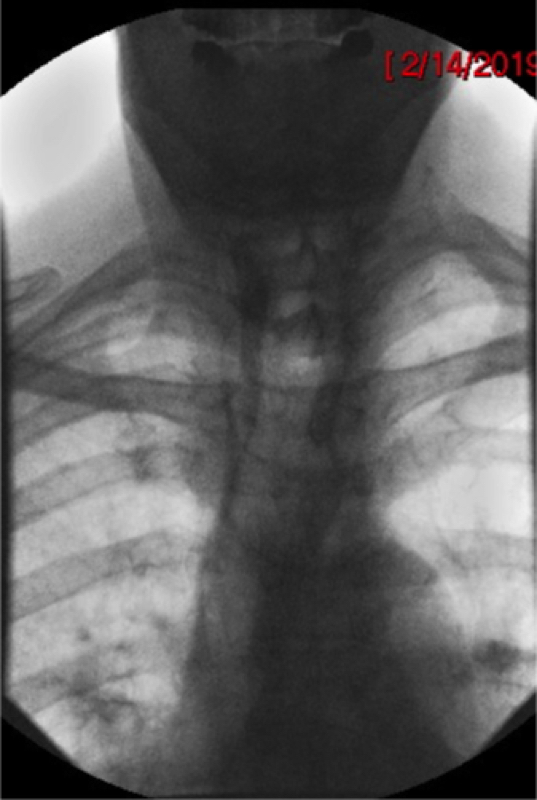

- For AP views, center the fluoroscope on the patient’s neck and collimate to include the mouth and upper thoracic esophagus

(key image 2).